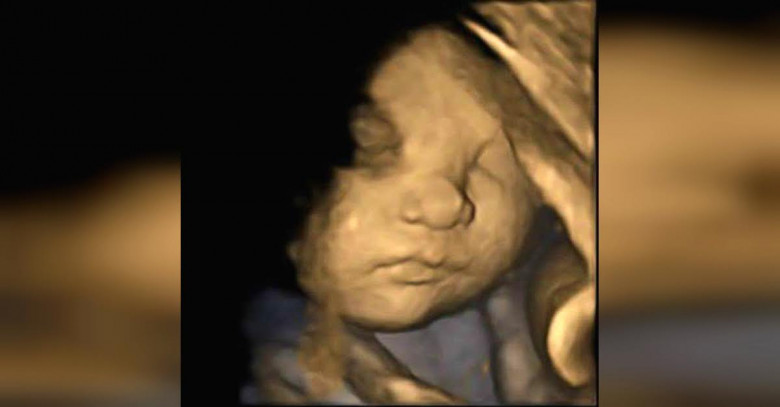

Врачи увидели на снимке УЗИ нечто странное. Тогда мама сделала то, чего от нее никто не ожидал!

Результаты первого же УЗИ показали некоторые отклонения в развитии ребенка. А более серьезное обследование выявило, что у девочки синдром Дауна. Кроме того существовала большая вероятность других отклонений в развитии: ребенок мог родится слепым или глухим.

Врачи честно проинформировали о результатах исследования и посоветовали прервать беременность. Биологические родители не хотели иметь проблем с будущим ребенком и прислушались к совету медиков. Они отказались от будущей девочки, но Андреа решила дать ребенку шанс.

Суррогатная мать решила выносить девочку и оставить ее себе. На протяжении всего срока беременности Андреа находилась под наблюдением врачей, но несмотря на все меры предосторожности, здоровье девочки находилось под угрозой. В первые несколько часов после рождения маленькая Дэлани перенесла несколько операций!